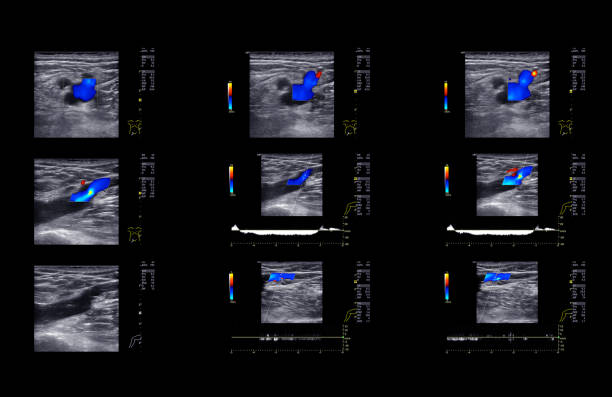

경동맥 초음파 검사는 초음파 기계를 사용하여 경동맥의 상태를 확인하는 검사입니다. 이 검사는 무해하고 비침습적이며, 빠르게 수행할 수 있어 환자에게 불편함을 주지 않습니다. 검사 과정은 다음과 같습니다.

- 초음파 프로브는 고주파 소리파장을 방출하여 경동맥의 이미지를 생성합니다.

- 이미지를 컴퓨터 모니터에 표시하여 의사가 경동맥의 상태를 시각적으로 확인할 수 있습니다.

검사 결과를 해석할 때, 의사는 다음 사항을 고려합니다.

- 경동맥의 크기와 형태: 경동맥이 충분히 넓고 매끄럽게 유지되는지 확인합니다.

- 혈류 속도: 혈액이 경동맥을 흐르는 속도를 측정하여 혈액순환에 이상이 없는지 확인합니다.

- 혈액 응고물질의 존재: 콜레스테롤과 혈액 응고물질이 경동맥 벽에 쌓여 있는지 확인합니다.